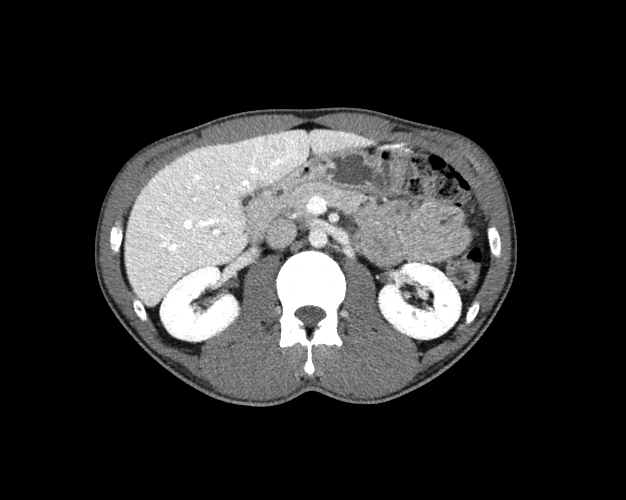

Body

Covers abdominal CT anatomy.